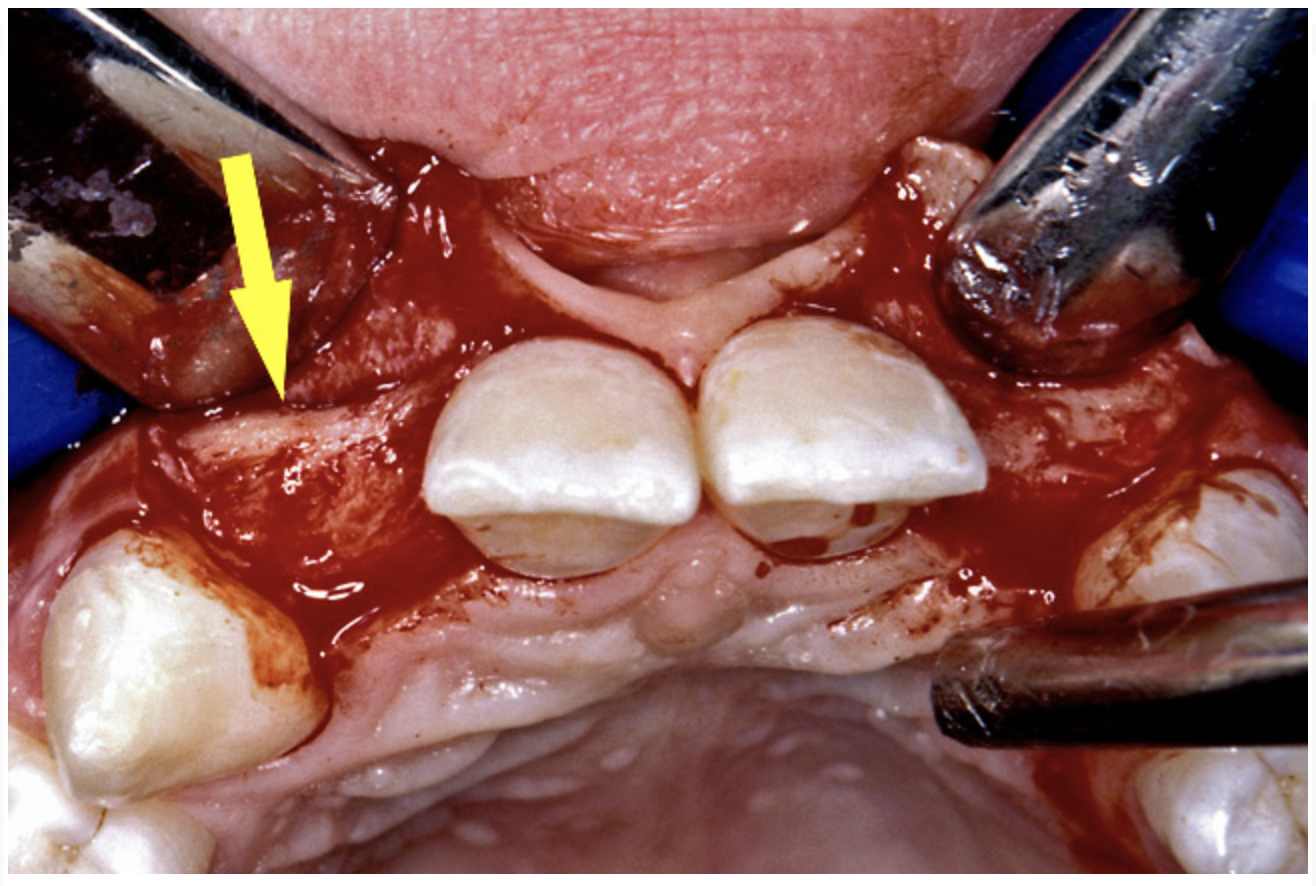

Before the day of surgery, the patient was seen by the orthodontist for the removal of the orthodontic brackets. The patient still was not pleased with the position of the two centrals, and it was determined that this would be addressed after implant placement (Figure 13A). The anatomical variations of the crestal tissue and lack of interdental papilla can be appreciated in the close-up views of the right and left sites (Figure 13B and 13C). There were no surprises on the day of surgery as all of the decisions were made during the planning phase, before the scalpel ever touched the patient. The occlusal view of the CT 3D model revealed the wider alveolar ridge on the right side and thinner crest on the left side (Figure 14A). This was confirmed when the full thickness mucoperiosteal flaps were elevated, and the underyling bone revealed (Figure 14B). The tooth-borne templates were designed to facilitate the drills and drilling sequence specific to the diameters of the predetermined implants (Figure 15A). Each template contained an embedded 5-mm long stainless steel tube, which was approximately 0.2-mm wider than each drill (just wide enough to allow for the drills to rotate freely). Once positioned over the natural teeth, the template was secure and offered precision accuracy in transferring the implant locations from the original software-designed plan, allowing the potential for internal and external irrigation (Figure 15B).

Figure 13a  Before implant surgery, the orthodontic brackets were removed, revealing (A) the position of the centrals, and (B, C) the anatomical variations of the crestal tissue and lack of interdental papilla.

Figure 13a

Figure 13b  Before implant surgery, the orthodontic brackets were removed, revealing (A) the position of the centrals, and (B, C) the anatomical variations of the crestal tissue and lack of interdental papilla.

Figure 13b

Figure 13c  Before implant surgery, the orthodontic brackets were removed, revealing (A) the position of the centrals, and (B, C) the anatomical variations of the crestal tissue and lack of interdental papilla.

Figure 13c